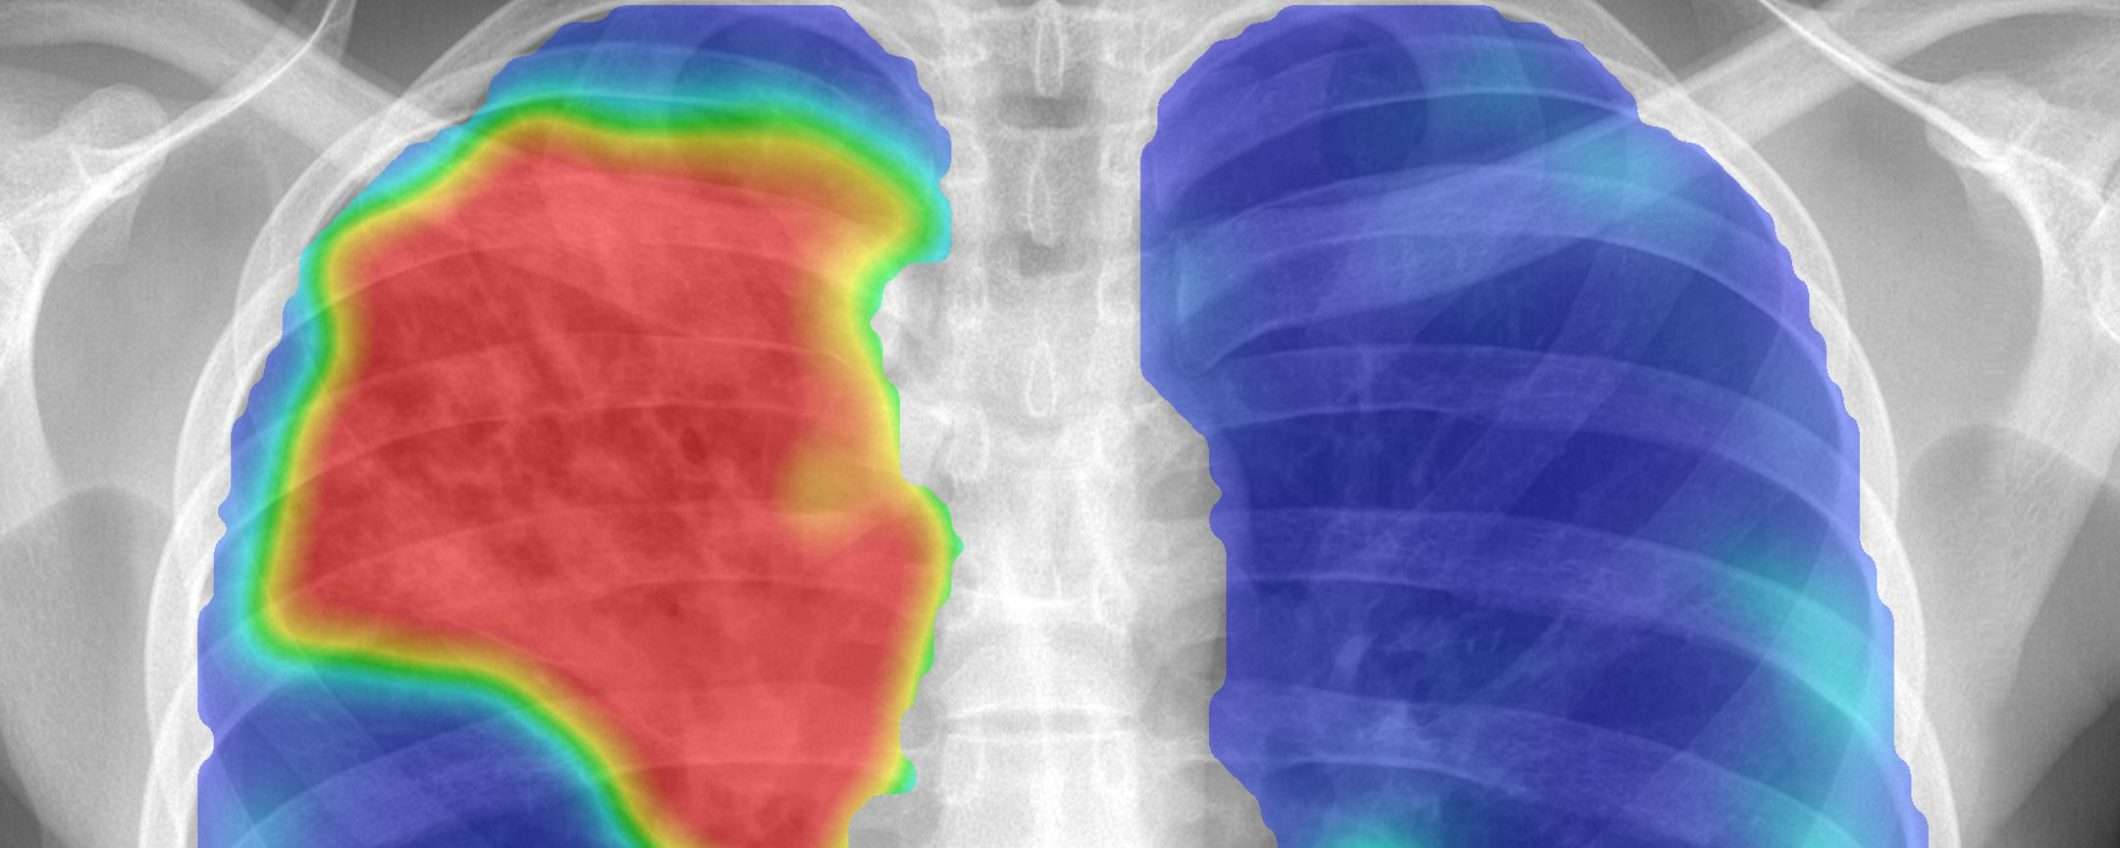

Ho studiato fisica e ho completato un dottorato di ricerca in analisi della diagnostica per immagini nel 1996, sviluppando programmi per computer che analizzano le radiografie del torace sfruttando l’intelligenza artificiale (IA). Alla fine degli anni ’90 volevamo mettere i radiografi digitali del torace con software di IA in Paesi dove la tubercolosi era molto diffusa, perché permette uno screening più veloce e più ampio, senza la necessità di sviluppare immagini su pellicola. Tuttavia, le apparecchiature di radiografia erano troppo costose all’epoca.

Nel 2012, il ‘deep learning’ (apprendimento profondo) ha preso piede, rendendo più popolare l’utilizzo di IA nella diagnostica per immagini. Mi sono trasferito per lavorare in un’università nei Paesi Bassi orientali, e lì ho creato un gruppo di 70 ricercatori per l’analisi della diagnostica per immagini. Cinque anni fa abbiamo iniziato a lavorare con i reparti di patologia per digitalizzare le immagini. Il problema è che, se conservate per uso medico, queste immagini molto grandi occupano tantissimo spazio. Pertanto, i reparti sono costretti in qualche modo a cancellare tutte le immagini dopo tre mesi, impedendoci di usarle per il deep learning. Ora che progressivamente i sistemi di archiviazione stanno diventando più economicamente accessibili, stiamo per risolvere questo problema. Sono certo che entro 10 anni a questa parte tutti i reparti di patologia saranno digitalizzati.

In Svezia è stato condotto uno studio di simulazione in cui è stato usato il più recente sistema IA di mammografia. I ricercatori lo hanno paragonato ai metodi di cura tradizionali. Hanno scoperto che il sistema di intelligenza artificiale funzionava come i radiologi dell’ospedale superando addirittura le prestazioni di alcuni. Così, hanno proposto di permettere che una grande percentuale di mammografie venisse letta solo dal sistema di IA. Se il sistema rilevava un problema, lo avrebbe notificato in modo che un radiologo potesse investigarlo.

La simulazione ha dimostrato che questo procedimento funziona. Tuttavia, non è stato implementato. Fu sostenuto invece che l’ospedale avrebbe dovuto fare una sperimentazione prospettica. Una sperimentazione può costare facilmente intorno ai 10 milioni di euro, per cui avevano bisogno di trovare ingenti finanziamenti. La sperimentazione avrebbe richiesto anni. Sono sicuro che quando avranno completato la prova, il software di IA avrà fatto così tanti progressi che questa tecnologia convalidata prospetticamente sarà già obsoleta.

Questa è la sfida che dobbiamo affrontare: dobbiamo convalidare i sistemi prima che possano essere utilizzati, ma ciò richiede tempo a causa delle normative, e nel frattempo questi sistemi stanno rapidamente migliorando.